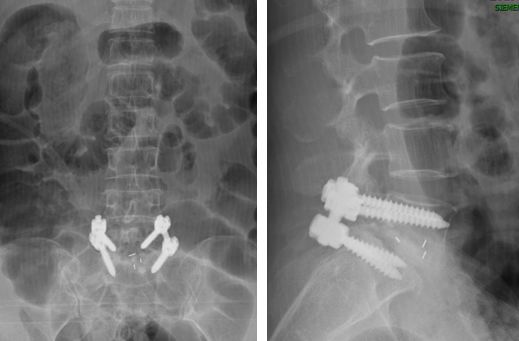

术后腰5椎体

完全复位

脊髓压迫

完全解除

腰椎内

固定术后

螺钉内固定